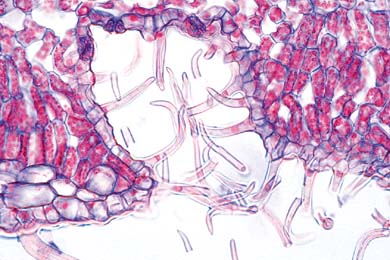

Mikropräparate